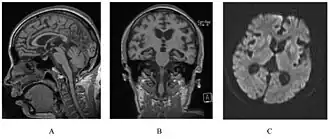

![]() У человека с наследственным прионным заболеванием наблюдается атрофия мозжечка. Это очень типично для синдрома ГШШ | |

Синдром Герстмана — Штраусслера — Шейнкера (Gerstmann-Sträussler-Scheinker syndrome) — очень редкое, обычно семейное, смертельное нейродегенеративное заболевание, поражающее пациентов в возрасте от 20 до 60 лет. Классифицируется как трансмиссивная спонгиоформная энцефалопатия, причиной заболевания является мутация гена прионового белка. Впервые было описано австрийскими неврологами Йозефом Герстманом (1887—1969), Эрнстом Штраусслером (1872—1959) и Ильёй Шейнкером (1902—1954) в 1936 году.

Синдром встречается у лиц в 40-50 лет и характеризуется, главным образом, мозжечковой атаксией, расстройствами глотания и фонации, прогрессирующей деменцией на протяжении от 6 до 10 лет (средняя продолжительность болезни составляет 59,5 месяцев), после чего наступает смерть. Инкубационный период длится от 5 до 30 лет.

Морфологические изменения при этом синдроме аналогичны обычным трансмиссивным подострым спонгиоформным энцефалопатиям. Отличительной его чертой является наличие большого количества концентрических амилоидных пластин, которые выявляются чаще в молекулярном слое коры мозжечка, но также их можно обнаружить и в коре мозга. Иммунопозитивные бляшки могут быть величиной от 150 до 500 микрон в диаметре. Они слабо PAS-положительны и редко показывают зелёное двойное лучепреломление при окрашивании конго красным. Сходство с болезнью Альцгеймера заключается в наличии нейрофибриллярных структур в цитоплазме нейронов. Отличительной чертой является то, что главный белковый компонент амилоидных ядер — это прионный белок PrP, а не AB-пептид.